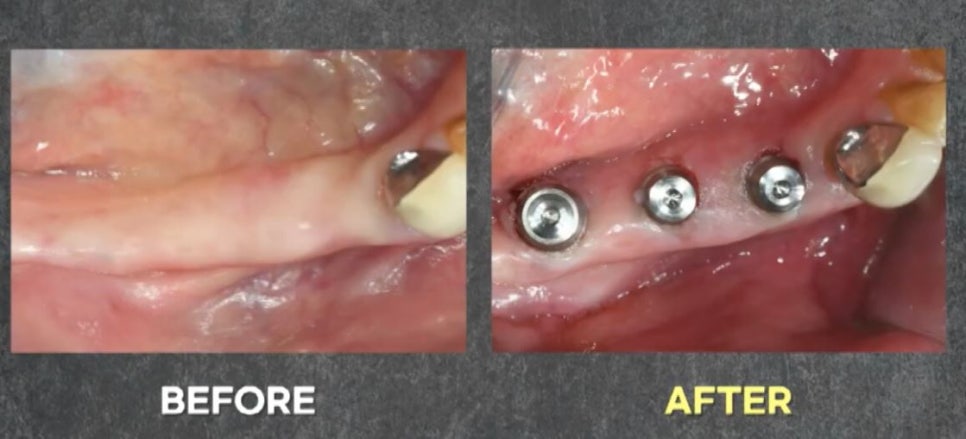

먼저 무절개 임플란트를 위해

매우 얇은 진단핀을 삽입합니다.

진단핀 삽입 직후의 모습을 보면

절개가 전혀 없이 깨끗한 모습을 확인할 수 있습니다.

출혈과 붓기 없이

깨끗한 상태죠~?